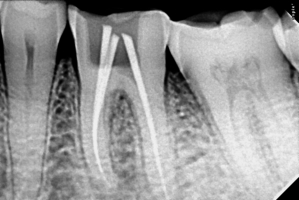

- Advanced Technology – Use of digital X-rays, rotary endodontics, and laser-assisted techniques for precision.